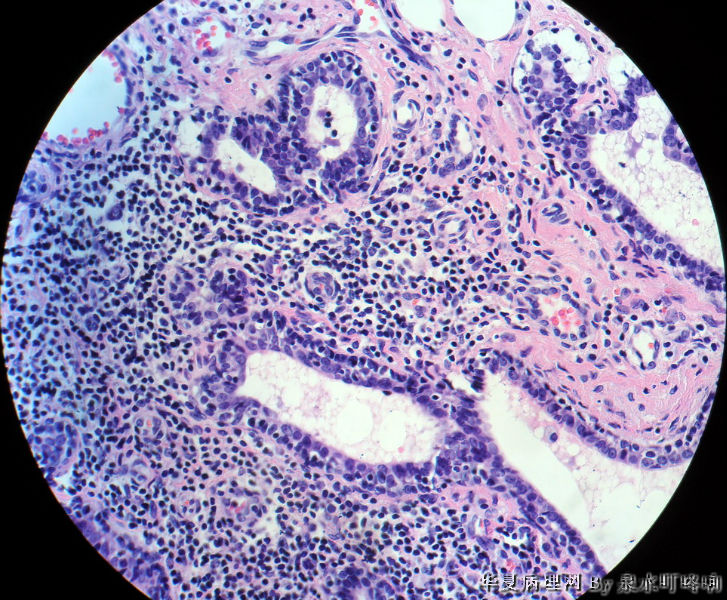

120213,女,23岁,右乳腺肿物半年,术中见肿物为多房性囊性肿物,内容黄色粘稠液体。

大体:灰白囊性肿物一个,大小约3×2×1.9厘米,局部囊壁增厚。

标签:乳腺腺病 导管扩张囊性变 淋巴细胞性乳腺炎

淋巴细胞性乳腺炎并导管扩张性囊性变。

乳腺小叶炎症导致小叶结构发生变形,有的腺泡萎缩,有的导管扩张,间质内淋巴细胞、纤维组织增生,都是炎症性适应性病变。

1.图像中有囊性增生,2.有腺病的结构,3.同时在低倍中可以看到有瘤样的结构,高倍中以腺肌上皮增生为主,未见核分裂,也未见恶性的现象,因此诊断乳腺的腺病瘤更为合适。

低倍小叶结构存在,炎细胞,导管扩张=炎症,考虑导管扩张症。